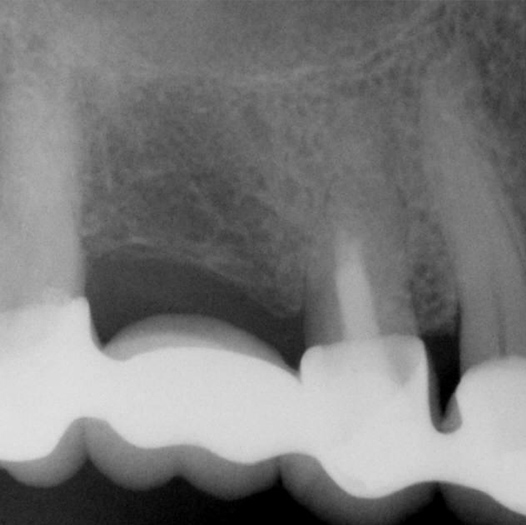

Before

Before Root Canal treatment